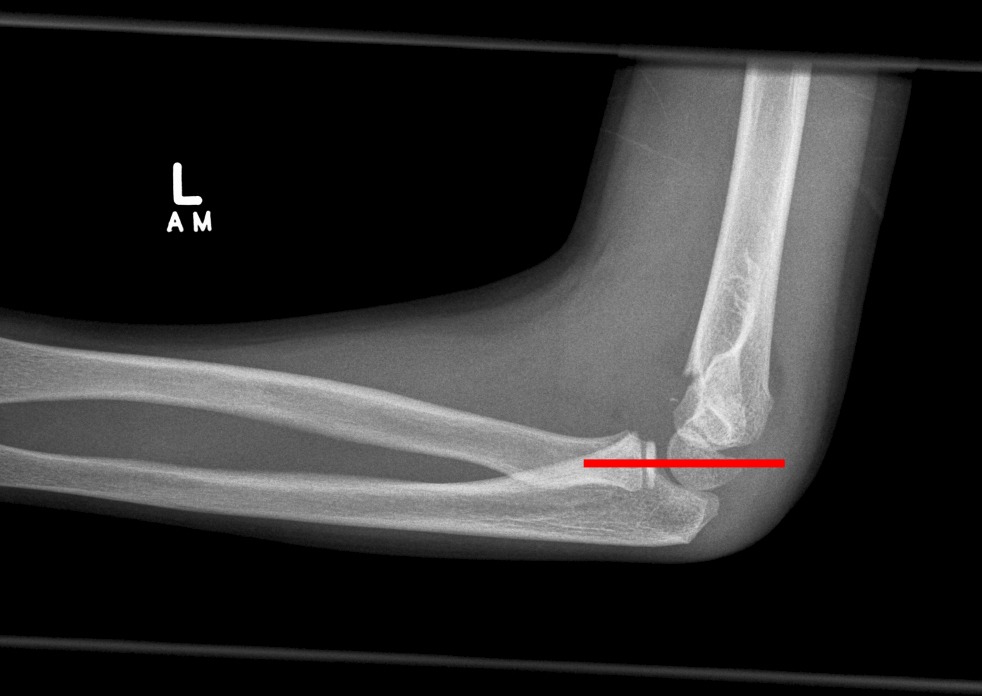

5. Check the radio-capitellar line

Draw a line through the middle of the proximal end of the radius – it should bisect the capitellum in lateral and AP views.

Displacement indicates a radial head dislocation.